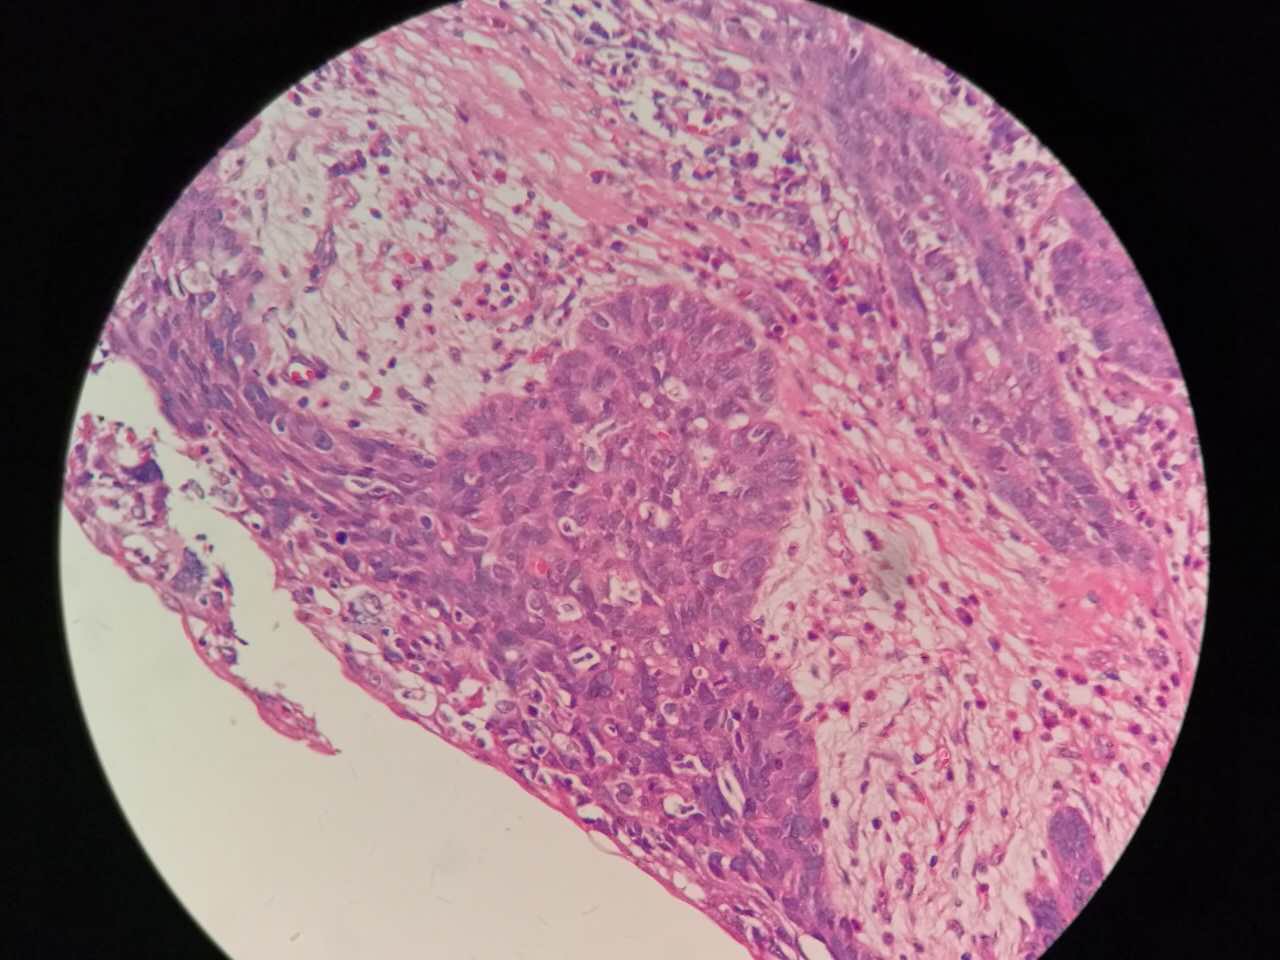

鳞癌

支气管粘膜鳞癌

结构紊乱,细胞异型

支气管鳞癌

复层排列,细胞有很多层

基底侧边界清楚

鳞癌生长,呈巢团状

巢团边界大多清楚

巢团可以很大,中央血供不足,就会坏死

中央红色的,有碎核

这个鳞癌不是早期

坏死也可以很大

较大的粉红区都是坏死,可以看出坏死是因为巢团大,中央坏死

下图是放大

鳞癌的核质比浸润性腺癌要紫兰一点儿

核仁也可以见到

但核仁不如浸润性腺癌明显